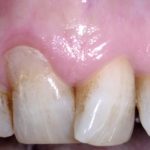

Restoration Guided Creeping Attachment (RGCA): approccio innovativo al trattamento di recessioni gengivali combinate ... Premium

Viene proposta una nuova tecnica come alternativa minimamente invasiva per il trattamento delle recessioni di classe I e II di Miller, anche combinate con...